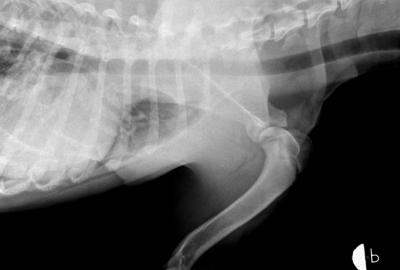

RTG Dysplazie kyčelního kloubu (DKK)